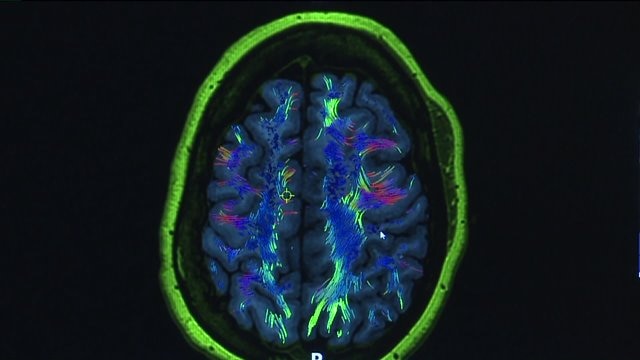

"The last frontier:" Study that`s unlocked 180 new regions of the human brain hailed as a major breakthrough